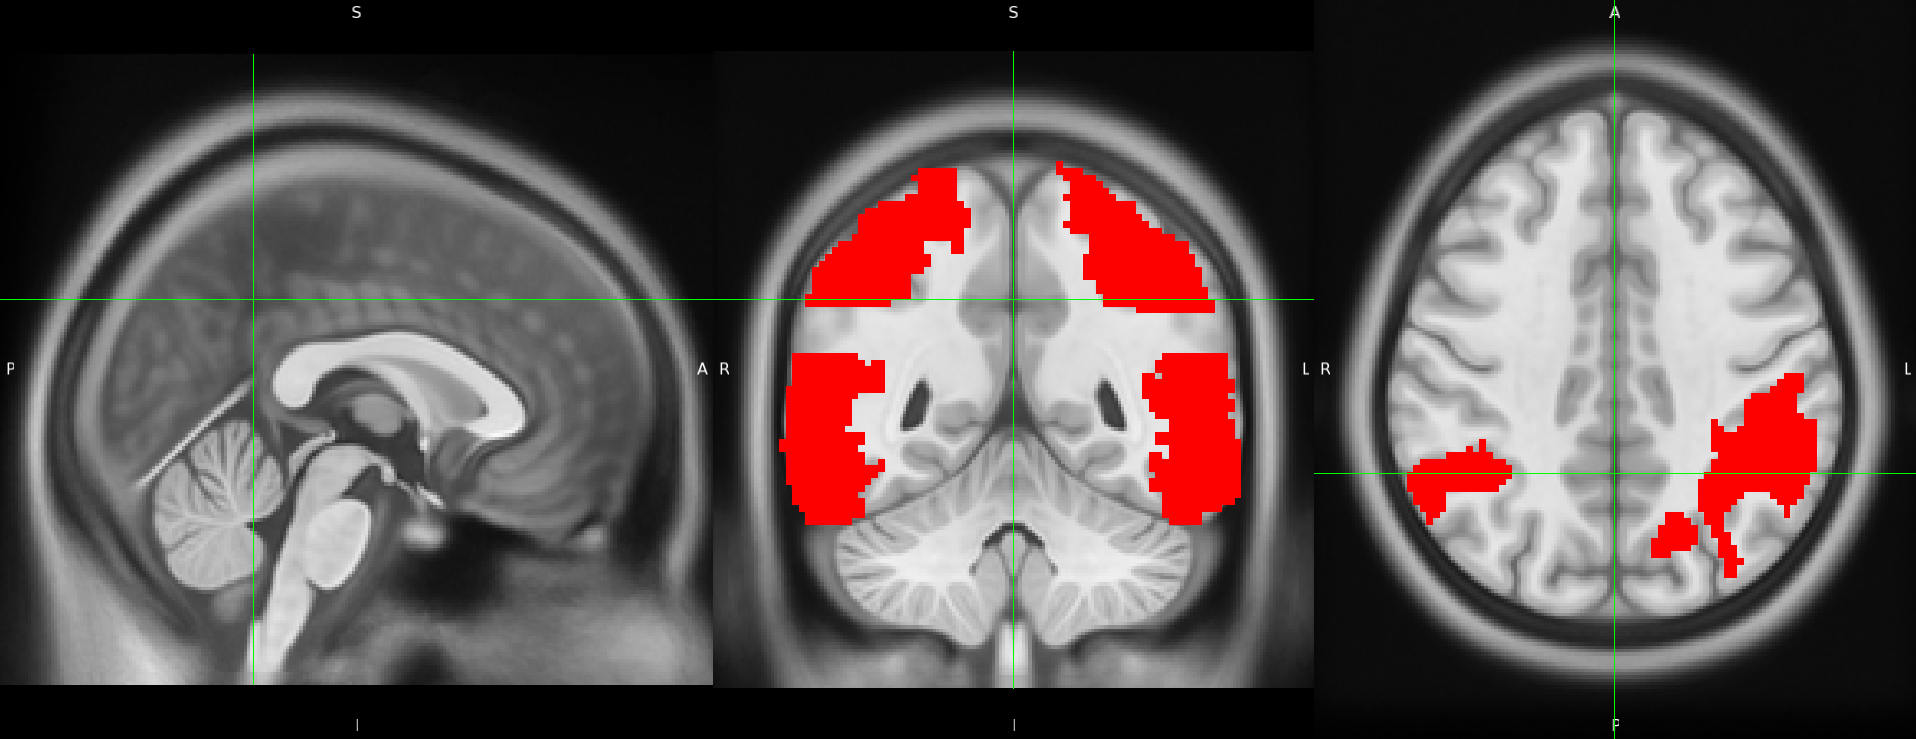

We here propose to simply generate new test sets by simulating hypometabolism on healthy images to have pairs of healthy (considered as ground truth) and abnormal images. For this purpose, we designed a mask corresponding to regions associated with AD (parietal and temporal lobes) (Landau et al., 2012) that were extracted from the third automated anatomical labelling (AAL3) atlas (Rolls et al., 2020). To obtain a realistic simulated image, we smoothed the mask with a Gaussian convolution filter with . We then reduced the intensity of the PET signal within the region defined by the mask by different factors to simulate various degrees of hypometabolism as illustrated in Figure 1. Having such pairs of images allows us to compare the pseudo-healthy image reconstructed by the model from images presenting anomalies with their corresponding healthy images (Figure 2), hence better evaluating the model capacity to synthesize pseudo-healthy images.

To ensure that the UAD model being evaluated can generalize to dementia other than AD, we also generated masks corresponding to five other dementia subtypes: behavioral variant frontotemporal dementia (bvFTD), logopenic variant primary progressive aphasia (lvPPA), semantic variant PPA (svPPA), nonfluent variant PPA (nfvPPA) and posterior cortical atrophy (PCA) based on the regions defined by Burgos et al. (2021b). All the details about the selected regions are available in Appendix B and a pipeline to use the simulation framework has been integrated into the ClinicaDL open-source software (Thibeau-Sutre et al., 2022).